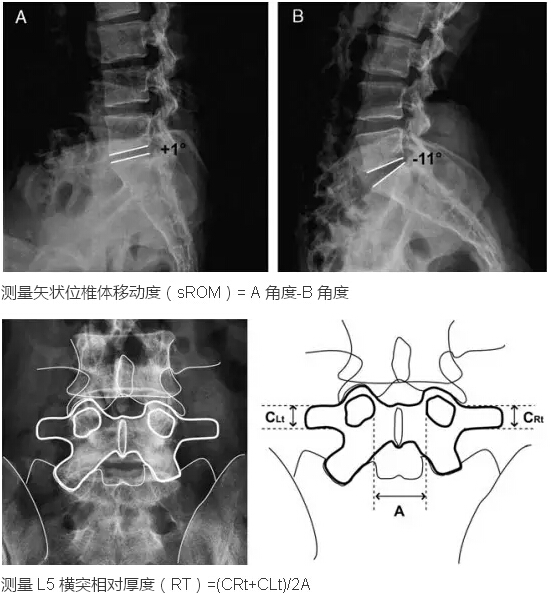

2. 术前影像学参数:椎间盘退变、椎间盘高度,矢状位椎体移动度(sROM)、L5 横突相对后度(RT)和髂嵴高度指数(IHI)。

在核磁共振 T2 上使用 Pfirmman 分级系统测定椎间盘退变,在侧位片上测定椎间盘高度和 IHI,在过屈过伸位片上测定 sROM,在前后位片上测定 RT。并评价了椎间盘退变与 sROM 的关系和 RT 与 sROM 的关系。运用多重 Logistic 回归分析评价腰椎间盘复发的危险因素。